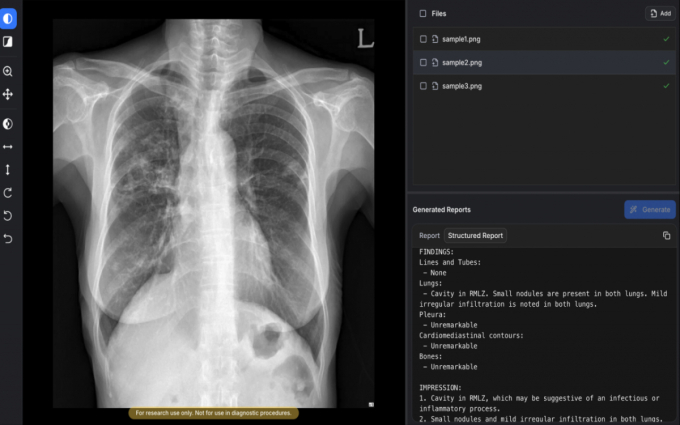

ÀÇ·á AI(ÀΰøÁö´É) ±â¾÷ ¼ûºøAI°¡ ½ÄǰÀǾàǰ¾ÈÀüó·ÎºÎÅÍ ÈäºÎX¼± ¿¹ºñ¼Ò°ß¼ »ý¼º ¼Ö·ç¼Ç '¿¡¾î¸®µå-¾¾¿¢½º¾Ë'(AIRead-CXR)¿¡ ´ëÇÑ 3µî±Þ ÀÎÇã°¡¸¦ ȹµæÇß´Ù°í 2ÀÏ ¹àÇû´Ù.

AIRead-CXRÀº ±¹³»¿Ü¿¡¼ È®º¸ÇÑ ¾à 1400¸¸°ÇÀÇ µ¥ÀÌÅ͸¦ ÇнÀÇØ ´Ù¾çÇÑ º´¿ø ȯ°æ¿¡¼ ÃÔ¿µµÈ PA(µÚ¿¡¼ ¾ÕÀ¸·Î Âï´Â ¹æ½Ä) ¶Ç´Â AP(¾Õ¿¡¼ µÚ·Î Âï´Â ¹æ½Ä) ÈäºÎX¼±¿¡ ´ëÇØ ¾ÈÁ¤ÀûÀ¸·Î ¿¹ºñ¼Ò°ß¼¸¦ Á¦°øÇÑ´Ù.

°ËÁõµÈ 57°³ ¼Ò°ß ¹× Áúȯ¿¡ ´ëÇØ ³ôÀº ¼öÁØÀÇ ÆÇµ¶º¸Á¶ ¼º´ÉÀ» Á¦°øÇÒ »Ó ¾Æ´Ï¶ó ÀÌ¿ÜÀÇ ´Ù¾çÇÑ ¿µ»ó ¼Ò°ßµµ ÇØ¼®¡¤¾ð±ÞÇÒ ¼ö ÀÖ´Ù. ÀÓ»ó ÇöÀåÀÇ ½ÇÁ¦ ¿öÅ©Ç÷ο츦 ¹Ý¿µÇØ ÀÇ·áÁøÀÌ º¸´Ù È¿À²ÀûÀ¸·Î ÆÇµ¶ ¾÷¹«¸¦ ¼öÇàÇÒ ¼ö ÀÖµµ·Ï ¼³°èµÆ´Ù.

°ø°³µÈ ÀÓ»ó³í¹®¿¡ µû¸£¸é ÈäºÎ¿µ»ó Àü¹®ÀǵéÀÌ Æò°¡ÇÑ AI ¿¹ºñ¼Ò°ß¼ Æò±Õ ¼ö¿ëµµ´Â 85%·Î, ºñ±³ ´ë»óÀÎ ±¸±Û µö¸¶ÀεåÀÇ AI ¸ðµ¨ 'MedGemma'(66.9%)¸¦ »óȸÇß´Ù. ȯ°¢(ÇÒ·ç½Ã³×À̼Ç) ºñÀ²Àº 0.3%·Î, MedGemma(9.7%) ´ëºñ ¿ì¼öÇÑ ¾ÈÁ¤¼ºÀ» º¸¿´´Ù.